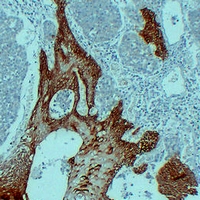

(Immunohistochemical analysis of Cytokeratin 14 staining in human squamous cell lung carcinoma formalin fixed paraffin embedded tissue section. The section was pre-treated using heat mediated antigen retrieval with sodium citrate buffer (pH 6.0). The section was then incubated with the antibody at room temperature and detected using an HRP conjugated compact polymer system. DAB was used as the chromogen. The section was then counterstained with haematoxylin and mounted with DPX.)

(Immunohistochemical analysis of Cytokeratin 14 staining in human esophageal squamous carcinoma formalin fixed paraffin embedded tissue section. The section was pre-treated using heat mediated antigen retrieval with sodium citrate buffer (pH 6.0). The section was then incubated with the antibody at room temperature and detected using an HRP conjugated compact polymer system. DAB was used as the chromogen. The section was then counterstained with haematoxylin and mounted with DPX.)